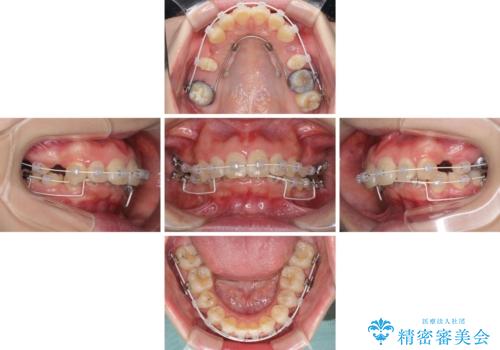

- 矯正装置

- 審美装置

- 飛び出した上顎前歯を気にして来院された患者様です。

下顎は左右2番目の歯が2本欠損しており、上下前歯の前後的な位置は著しくずれている状態でした。

骨格的にも上顎骨が前突傾向にあり、極端な過蓋咬合になっていました。

強い咬合力に抵抗するように歯を動かす必要があるにもかかわらず、上顎第一大臼歯が1本欠損しているため、治療は困難を極めることが予想されました。

上顎前突を改善するために上顎左右第一小臼歯を抜歯し、補助装置を用いて上顎臼歯が前方に移動しないように工夫しながら、表側のワイヤー装置にて歯列を整えていくこととしました。

矯正治療後には、上顎欠損部をオールセラミックブリッジにて補綴治療を行うこととしました。

予想通りに治療は困難を極め、その上途中来院されない時期があったため、非常に長期間に及びましたが、周囲の方々が驚愕するほど口元の印象を改善することができました。